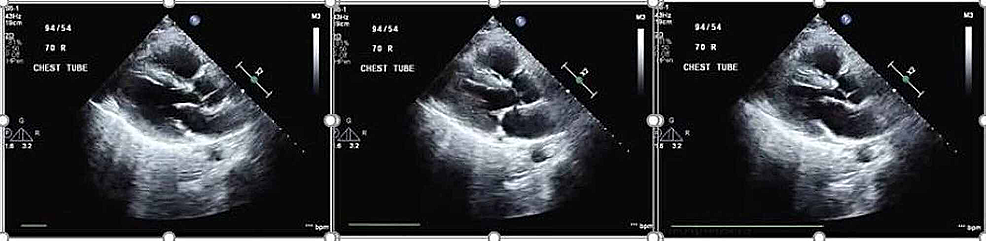

On arrival to hospital 2, he underwent immediate cannulation for femoro-jugular VV-ECMO and was started on an initial flow rate of 4100 ml/min, gas sweep of 11 L/min, goal oxygen saturation (SaO2) > 85% and PaO2 > 55 mmHg. He was also started on inhaled nitric oxide (iNO) at 20 ppm. Sedation and neuromuscular blockade were continued. A five-day course of dexamethasone (20 mg IV once daily) was given as well. A transthoracic echocardiogram demonstrated mild right ventricular dilation with hypokinesia of the mid-right ventricular free wall and left ventricular ejection fraction of approximately 60% (Figure 3).